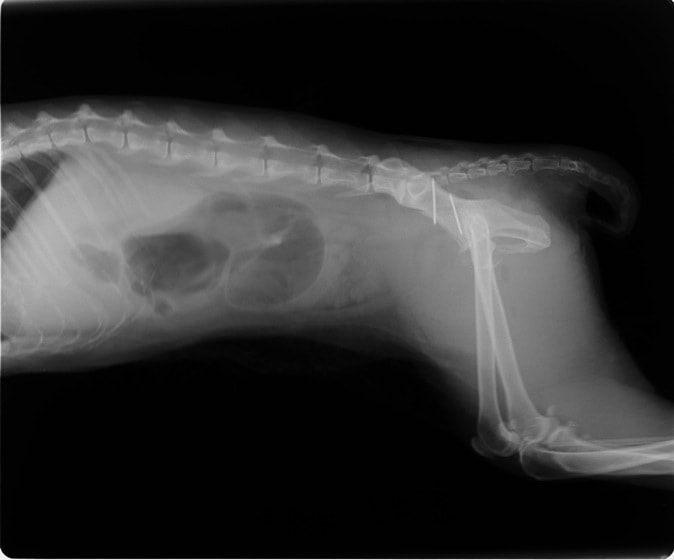

症例3:キルシュナーワイヤーのピンニングによる整復

ペルシャ猫 11ヶ月齢 雄

他院にて左大腿骨遠位の成長板骨折(salter-harrisⅠ型)が認められており、治療相談を目的として来院。当院にて、キルシュナーワイヤーを用いたピンニングにより骨折部位の整復を行いました。術後の経過は良好で、現在も経過観察中です。

術前レントゲン

術後レントゲン

機器

Arthrex社のターゲティングデバイスを用いてピンニングの位置を調整することで、確実な固定を行っています。当院ではこの手術器具以外にも、人の手術にも使用される様々な器具を導入し、手術精度を高め、また医療メーカーと新しい器具の開発、試作にも取り組んでおります。